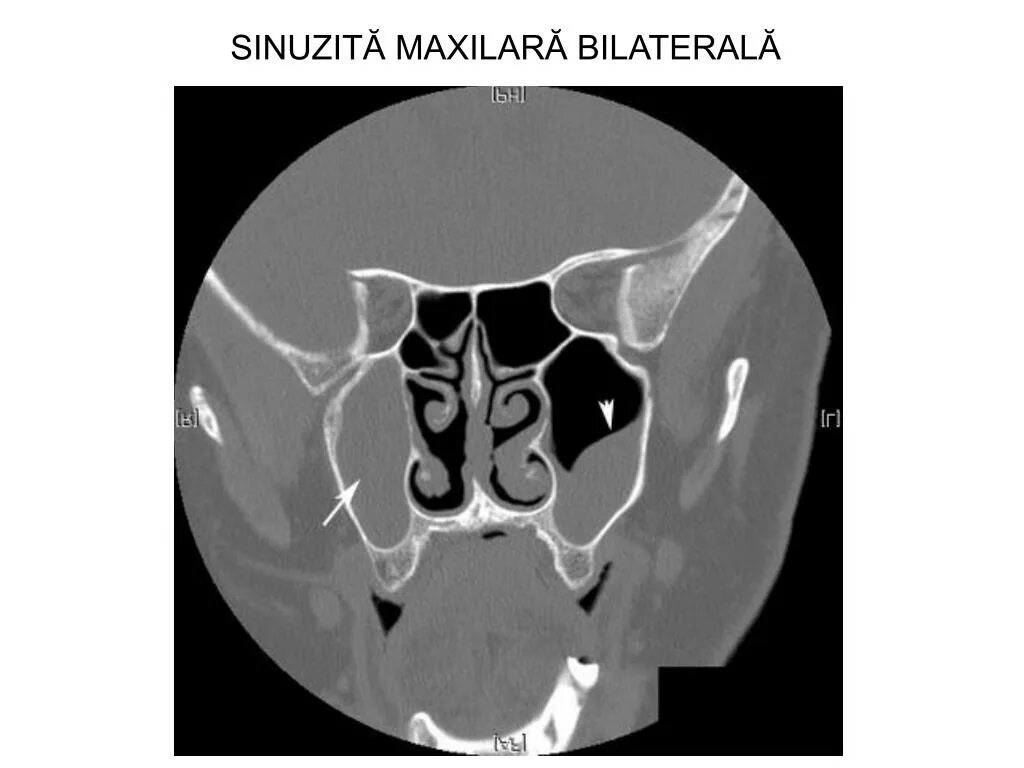

Синусит на кт